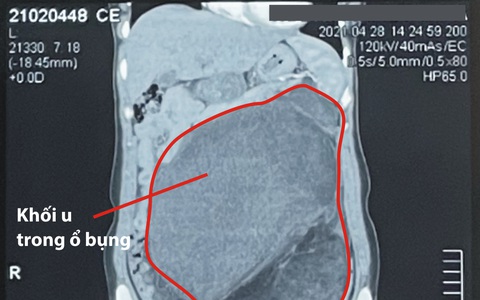

Vừa qua, Bệnh viện Đa khoa Tâm Trí Đồng Tháp phẫu thuật thành công cho bệnh nhân nữ N.T.K.T (45 tuổi, ngụ Thanh Bình, Đồng Tháp) bị khối u khổng lồ trong mạc treo đại tràng ngang nặng gần 3 kg.